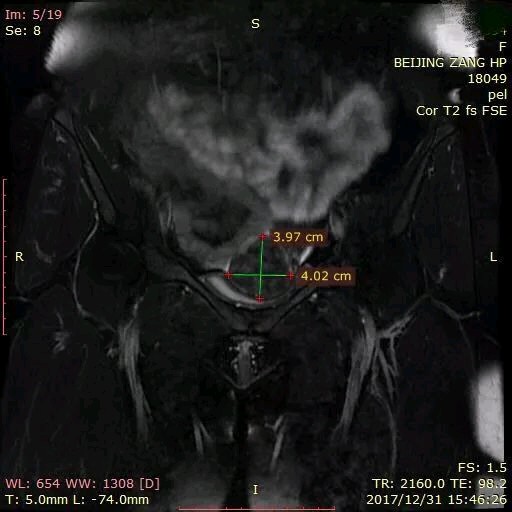

从光盘Dicom的图像上我清晰地看到了她的肌瘤目前只有一个,大概也就是4cm的大小,部位是6型的肌瘤,整个肌瘤基本上都是凸出于子宫外,这样的肌瘤基本上对怀孕不会产生太大的影响的,我就建议她直接尝试带瘤去做移植。浆膜下肌瘤在怀孕以后最大的风险就是在孕早期以后快速增大,有的时候甚至体积可能会增大数十倍,有10~15%的可能会发生红色变性的风险,但是大多数的情况下保守治疗就好。这样的风险是要好过做手术处理肌瘤带来的风险。